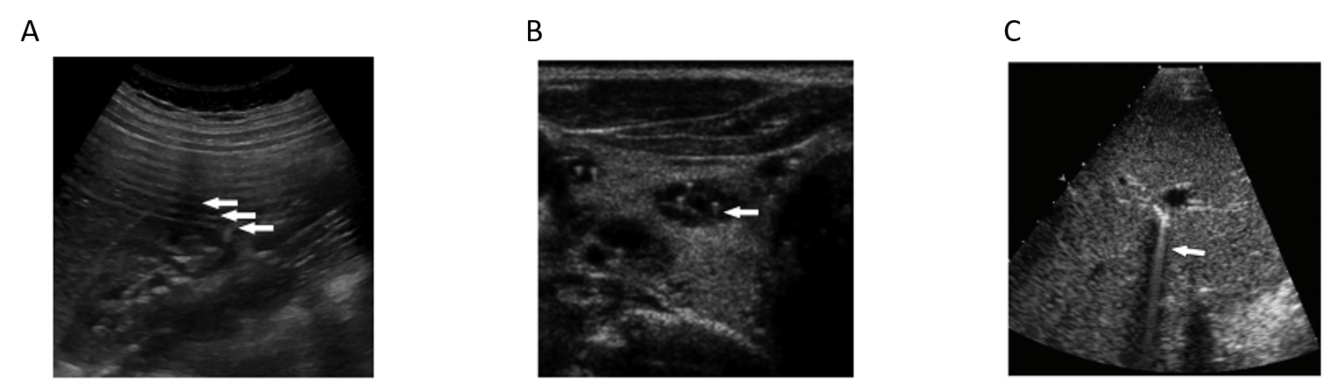

The artifact shown is reverberation caused by back and forth reflection of the ultrasound beam between 2 closely spaced interfaces. These reverberation echoes appear as multiple equally spaced lines, which decrease in intensity with increasing depth. This artifact is often caused by highly reflective interfaces, e.g., metallic objects or calcification in tissues.

reverberation artifact:

multiple equidistance echoes

comet tail artifact is a form of reverberation, but the two parallel highly reflective surfaces are closer together –> sequential echoes are closely spaced

spce between reflectors may be < SPL (minimal distance needed for axial res)

Reason you see a triangle and not a square: later echoes get attenuated and have decreased amplitutde. Decreased amplitude is manifested on the displayu as decreased width. So you get a tapering triangle

ring down artifact

sound wave encounters fluid trapped between a tetrahedron of air bubbles. The vibrations create a nearly continuous sound wave transmitted back towards the probe